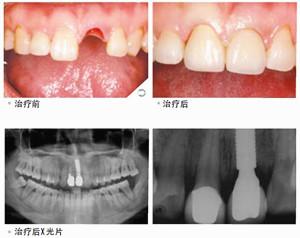

種植牙也叫人工種植牙,并不是真的種上自然牙齒,種植牙而是通過醫(yī)學(xué)方式,將與人體骨質(zhì)兼容性高的純鈦金屬經(jīng)過精密的設(shè)計(jì),制造成類似牙根的圓柱體或其他形狀,以外科小手術(shù)的方式植入缺牙區(qū)的牙槽骨內(nèi),經(jīng)過1~3個(gè)月后,當(dāng)人工牙根與牙槽骨密合后,再在人工牙根上制作烤瓷牙冠。因不具破壞性,種植牙已被口腔醫(yī)學(xué)界公認(rèn)為缺牙的修復(fù)方式。種植牙由于人工牙深植牙骨內(nèi),可承受正常的咀嚼力量,功能和美觀上幾乎和自然牙一樣,因此,被人們稱為人類的第三副牙齒。